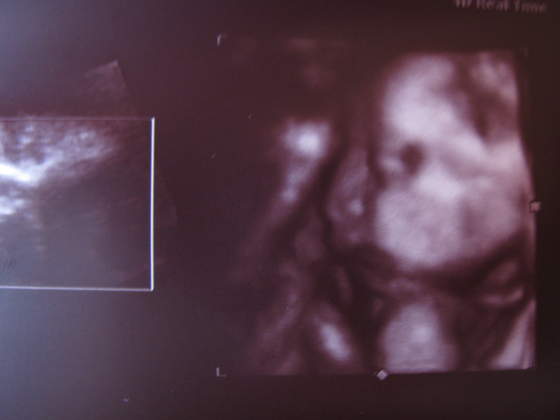

paula-śliczna duża babka i te murzyńskie usta ech!

ale lekarka mnie uspokoiłanadika wstydziosze z Natanka:-)Cudeńko z piękną wagąA co lekarz mówił na tą pępowinę?

Filipek![]()